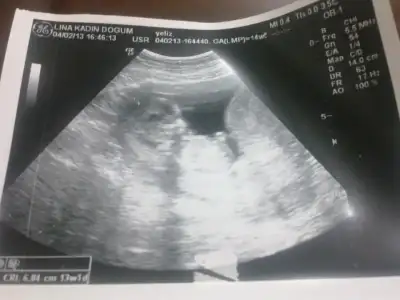

Orkdm,bugün 9 şubat ve nihayet geldi bizim kontrol gününümüz.Gittik işte.Direk yattım ultrasona bakdı doktor.Uzun süre-once kafasına,sonra omurgasına,bacaklarına-her şeyine bakdı)Kalp atışları iyi-sağlığı maşAllah yerinde.Ben size cinsiyeti söyleyimmi-söylemeyim mi?Söylemeyim!dedi doktor)dedim-hayır!Söyleyin!Tamam o zama - dedi-100/98 cinsiyeti,sinsiiii-yeeee-tiiii, ben bişeyler görüyorum da yine bakaaayım.Cinsiiiyeeeetiiii-aaaa yooook kordonmuş,kordon geçiyor(((göremiyorum.Ben cinsiyet organını tam göreyim,öyle söylerim. 3 haftadan sonra gelirsin,söylerim-dedi...(bebek doğunca cinsiyet organını o zaman göreceyi gibime geliyor))))

Ben delirecem yaaaaaahhh)))ben net olarak her şeyi gördüm((kordonu pardon pipiden ben ayıramam,ama o doktor- da mı ayıramıyor(((bir de ultrason fotografını ekleyim de,orkdeciyim bak bişey görüyonmu))16+1 hafta $ABCD0001.webp